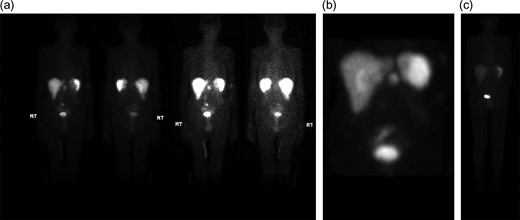

Initial inpatient evaluation started with pan endoscopy. Upper endoscopy demonstrated a Billroth II anastomosis with patent efferent and afferent limbs and no evidence of marginal ulceration or malignancy. Colonoscopy, likewise, was unremarkable. Radiographic evaluation with computed tomography of the abdomen and pelvis did not show evidence of pancreatic tumor or biliary ductal dilatation (Fig. 1). An octreotide scan, however, demonstrated increased activity near the head of the pancreas and abdominal aorta (Fig. 2 a-b). Endoscopic ultrasound did not fully evaluate the head of pancreas but showed no lesions in the left lobe of the liver, pancreatic body and tail. Capsule endoscopy then followed and was unremarkable. Despite being placed nil per Os, the patient’s diarrheal symptoms and hypokalemia persisted. Stool cultures obtained on admission demonstrated no growth.

Computed tomography scan of the abdomen and pelvis with intravenous contrast (Omnipaque 350TM, iohexol, 50 mL). No evidence of pancreatic mass or biliary ductal dilation was identified.